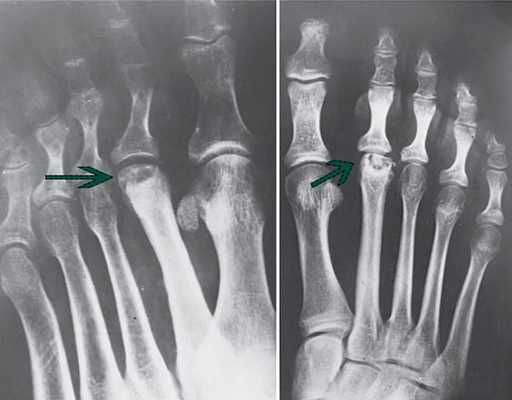

Рентгенологические признаки болезни Келлера. Поздние стадии заболевания: центральный коллапс и остеолиз головки.

Рентгенограмма на которой отмечается формирование крупного остеофита (стрелка) в области третьего плюснефалангового сустава.